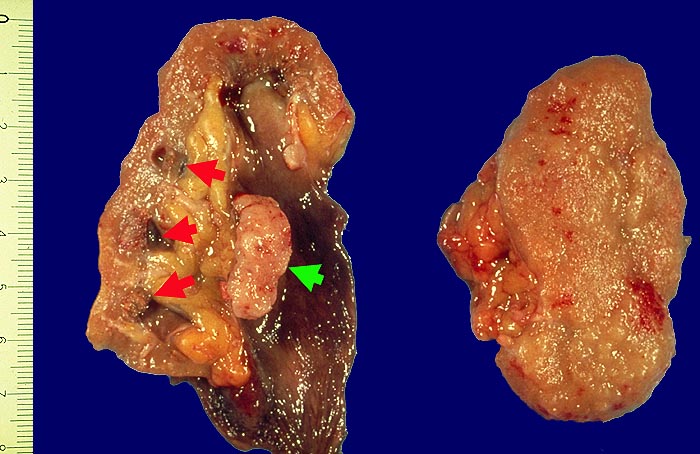

Pathomorphologisch unterscheiden sich Urothelkarzinome bei Phenacetinabusus nicht von sporadischen Urothelkarzinomen abgesehen von ihrer bevorzugten Lokalisation im Nierenbecken und der allenfalls ausserhalb des Tumors in der Harnwegsschleimhaut nachweisbaren Kapillarosklerose.

Morphologische Merkmale:

• Solider Tumor mit fokalen Entzündungsinfiltraten.

• Ureter mit verdickten Kapillaren (Kapillarosklerose).